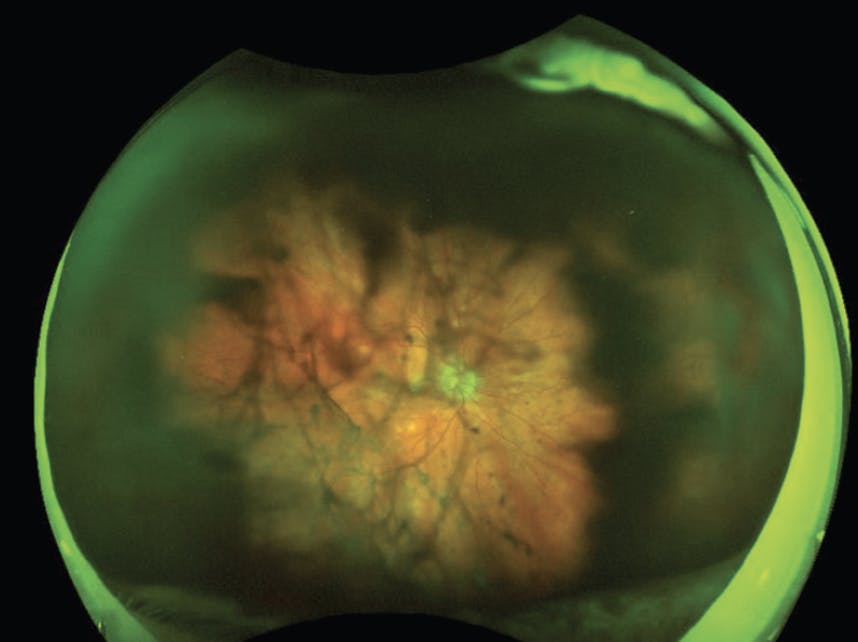

In rare cases, a fine needle aspiration biopsy (FNAB) or tissue sample of subretinal deposits, the retina, and/or the choroid can also help identify lymphoma (Figure 2).9 An FNAB can be performed through either a transvitreal or transscleral approach with a 25-gauge needle attached to the tubing and a syringe, but the surgeon may have difficulty accessing or visualizing lesions that are anterior. When a subretinal biopsy makes the most sense, use diathermy to create a retinotomy overlying or adjacent to the infiltrate and aspirate the subretinal material with a soft tip.

<p>Figure 2. A 73-year-old woman with a history of diffuse large B-cell lymphoma was referred for worsening vision. Given her presentation of hemorrhage and retinal whitening, an infectious etiology was considered; however, the lesion continued to grow despite repeated injections of antiviral therapy. A retinal biopsy confirmed diffuse large B-cell lymphoma and the intraocular manifestations were managed with intravitreal methotrexate.<br />

Image courtesy of Steven Yeh, MD, and Ghazala O’Keefe, MD</p>

Figure 2. A 73-year-old woman with a history of diffuse large B-cell lymphoma was referred for worsening vision. Given her presentation of hemorrhage and retinal whitening, an infectious etiology was considered; however, the lesion continued to grow despite repeated injections of antiviral therapy. A retinal biopsy confirmed diffuse large B-cell lymphoma and the intraocular manifestations were managed with intravitreal methotrexate.

Image courtesy of Steven Yeh, MD, and Ghazala O’Keefe, MD